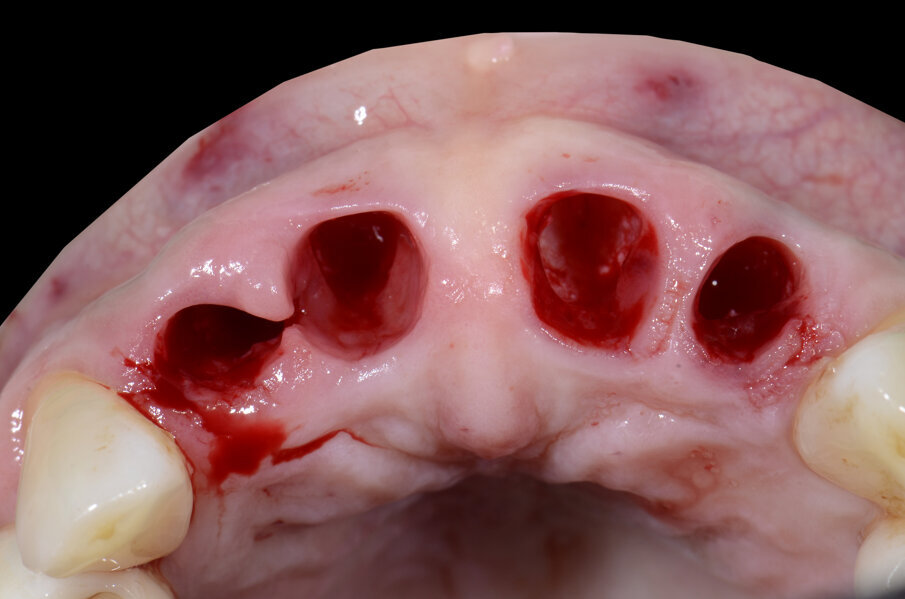

All’esame clinico presenta i quattro incisivi superiori malposizionati, con diastema per evidenti problemi parodontali. Perdita importante di supporto parodontale, presenza di tasche superiori a 6 mm, mobilità di tipo 2/3 su tutti i quattro elementi (Figg. 1-4).

Il piano di trattamento prevede l’estrazione degli elementi dentali, l’inserimento di due impianti e la realizzazione di una protesi fissa di quattro elementi. Il problema da gestire è quello della fase provvisoria. Non è ipotizzabile una protesi mobile e quindi programmiamo di inserire subito dopo l’intervento un provvisorio immediato. Questo ci consente di condizionare da subito i tessuti periimplantari e anche le zone dei ponti. Si rileva un’impronta digitale (Figg. 5, 6), e la programmazione degli impianti viene effettuata con un software di chirurgia guidata (Fig. 7) e la posizione degli impianti nello spazio biologico e nello spazio protesico viene fatta sulla base di una ceratura diagnostica (Figg. 8, 9). Inseriamo gli impianti virtuali nell’osso disponibile (Figg. 10-13) e in relazione all’aspetto protesico correggiamo l’asse di inclinazione degli impianti con componenti secondarie angolate a 17° (Figg. 14, 15). Questo ci consentirà di realizzare una protesi avvitata con i fori situati nella zona palatale.

Il nostro obiettivo è quello di riuscire a dare alla paziente un provvisorio immediato nell’arco di due ore. Questo diventa possibile perché abbiamo utilizzato un flusso digitale fin dall’inizio. In laboratorio vengono realizzate la dima chirurgica (Figg. 16, 17), la dima protesica (Fig. 18) e anche il provvisorio (Figg. 19-21) che contiene delle alette di riposizionamento. Il tutto gestito con modelli digitali sui quali saremo in grado di funzionalizzare il provvisorio post-chirurgico (tecnica DIL). In un caso come questo se utilizziamo un flusso digitale possiamo evitare subito dopo la chirurgia di rilevare un’impronta degli impianti inseriti. Infatti, utilizziamo una dima chirurgica che ci faciliterà le fasi di intervento. La dima ci consentirà di non fare lembi e nessuna incisione di rilascio (Fig. 22), dopo aver inserito gli impianti (BLX Straumann) (Figg. 23-31) e aver controllato il loro alloggiamento, inseriamo sugli stessi dei transfert da impronta (Fig. 32).

Fig. 31 - Visione occlusale impianti inseriti.